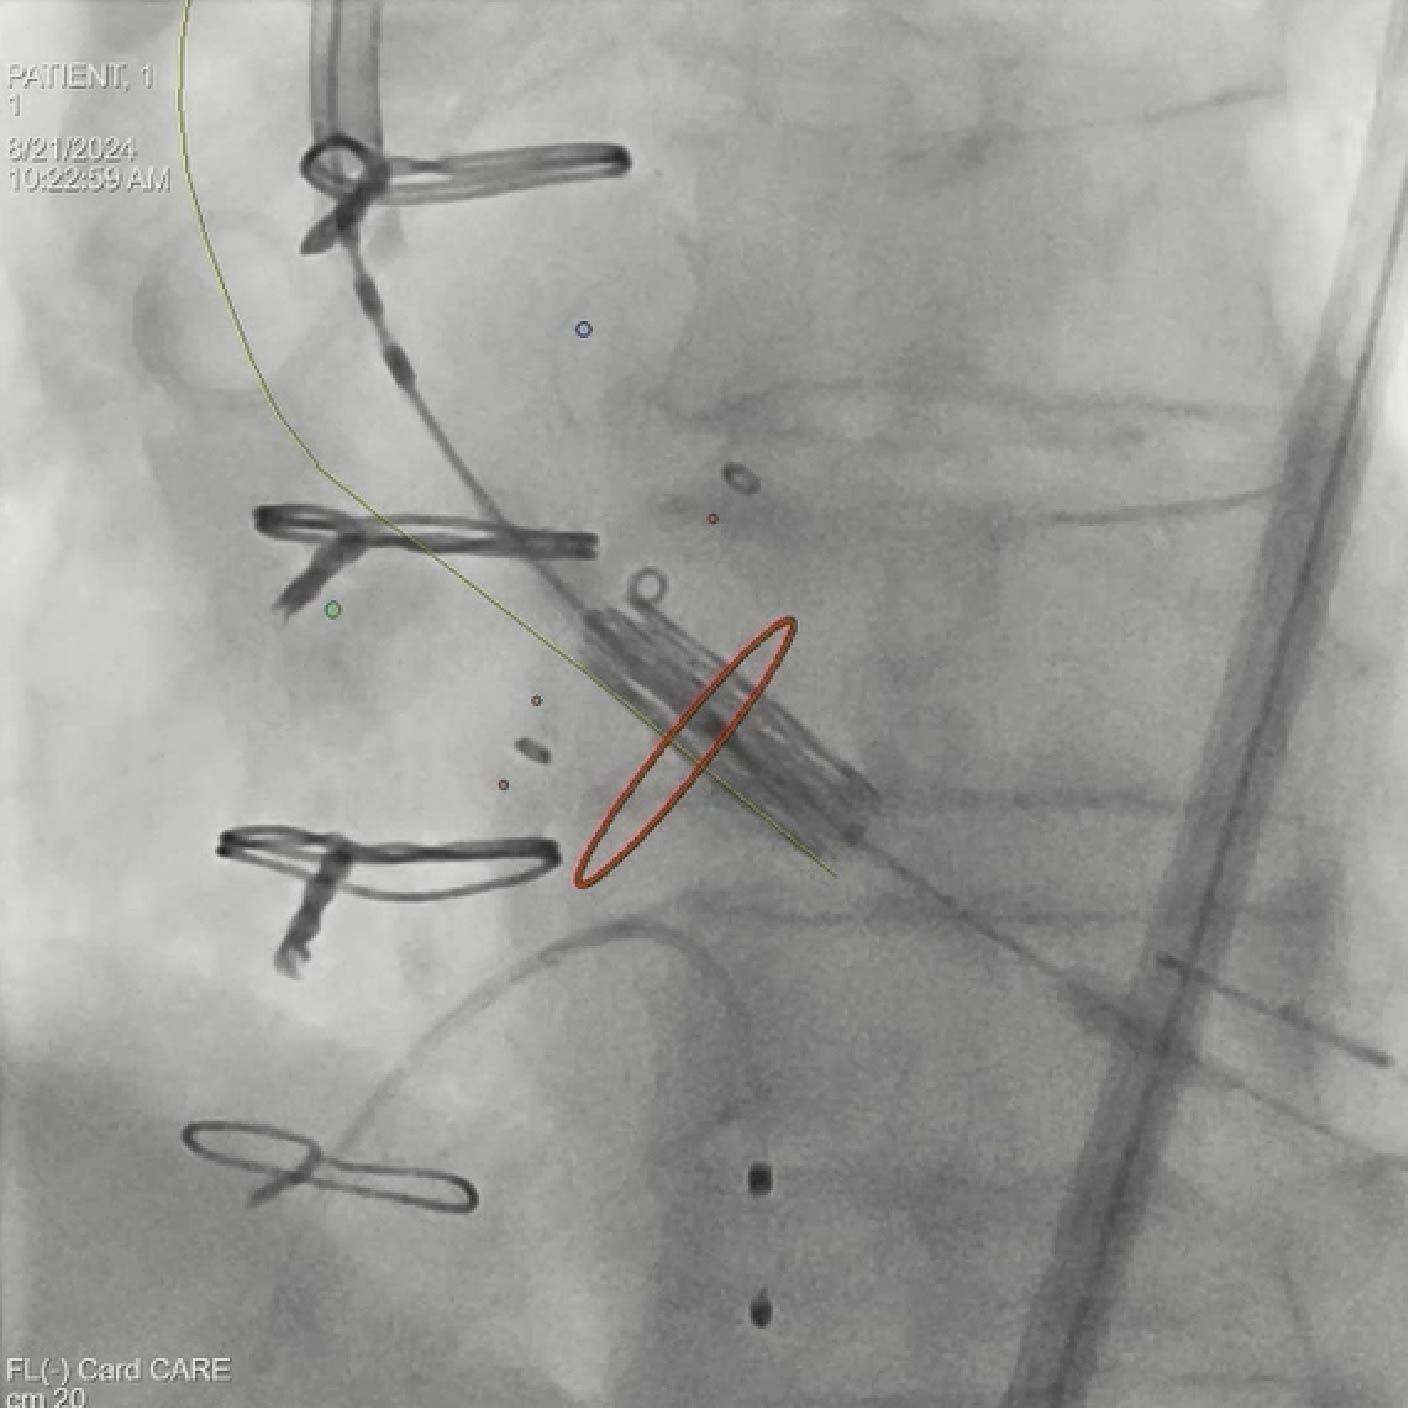

- Colocación del guía y del dispositivo con syngo Aortic Valve Guidance

Soluciones y características seleccionadas: ARTIS pheno, Case Flows, Una combinación preestablecida de configuraciones (angulación, disposición de la pantalla, etc.), personalizada para la colocación del dispositivo SENTINEL™*, reduce las interacciones con el sistema. Con Case Flows, una única interacción del usuario reemplaza el ajuste de hasta 6 configuraciones del sistema³. syngo 2D/3D Fusion - Aplicación para superponer la anatomía de la arco aórtico basada en tomografía computarizada sobre fluoroscopia en vivo, para apoyar la navegación del dispositivo. Se ha demostrado que la guía por fusión reduce significativamente el tiempo de despliegue del dispositivo SENTINEL™* y el uso de contraste⁴.

Soluciones y características seleccionadas: 3mensio (Pie Medical Imaging) Software semiautomatizado para asistir en la reconstrucción 3D de la válvula previamente implantada y la anatomía circundante, con el fin de determinar el abordaje ideal y el tamaño adecuado de la válvula. Su uso reduce el tiempo de planificación del TAVR¹ y los resultados de la planificación pueden exportarse para superposición en tiempo real durante la fluoroscopia.